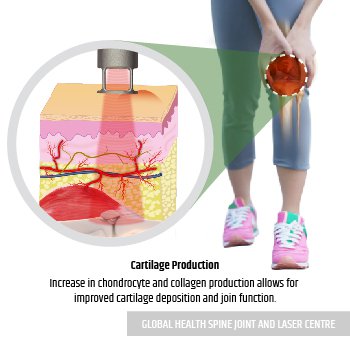

Laser Beam is applied to the knee for treating all damage.

Laser Beam increased oxygenated blood to the injured tissue accelerates tissue healing.

After Laser Treatment, cartilage deposition and joint functions are improved.